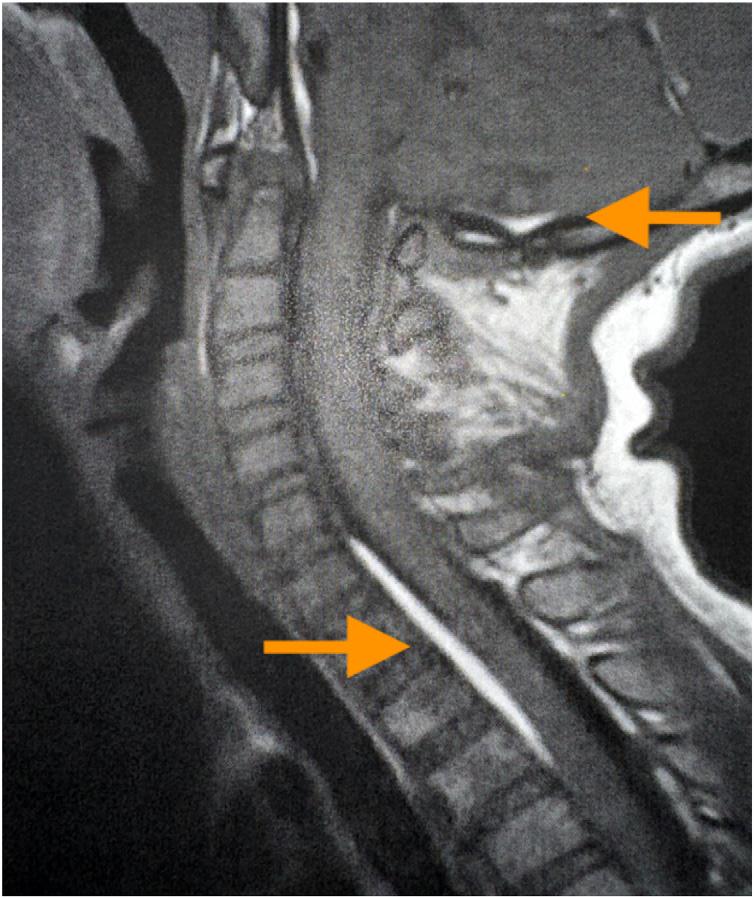

345 A Pediatric Case Report of Acute Torticollis Secondary to Atraumatic Cerebellar Hemorrhage

JA Enabore, R Vezzetti, G Hill